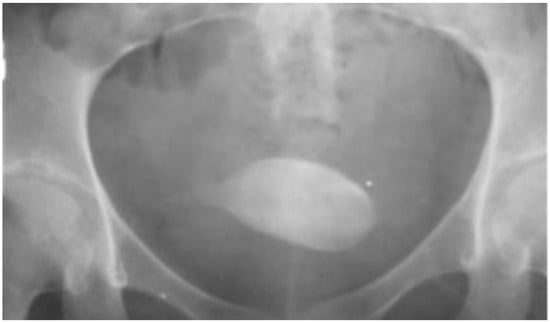

| 2 | 25 | F | pencil | urinary bladder | sexual stimulation | 5 weeks | UTI, LUTS | cystoscopy |

| 7 | 16 | F | pen | urinary bladder | sexual stimulation | 1 year | abdominal pain, pyuria | cystoscopy |

| 9 | 24 | F | pencil | urinary bladder | unknown | unknown | pyuria | cystotomy |

| 10 | 35 | F | pen | urinary bladder | unknown | unknow | abdominal pain, pyuria | cystotomy |